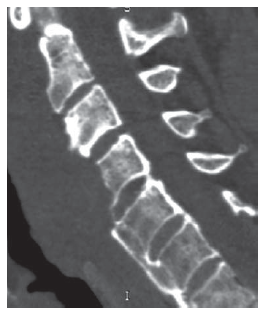

Длительность операции составила 185 мин, кровопотеря – 150 мл. Послеоперационный период проходил без осложнений. Результаты операции отражены на КТ-реконструкциях, выполненных на следующие сутки после операции (рис. 3). В раннем послеоперационном периоде отмечен регресс дооперационного болевого синдрома, дисфагии и дисфонии.

Рис. 3. Послеоперационная КТ шейного отдела позвоночника. Очаг гиперостоза удален. Компрессия глотки и гортани устранена